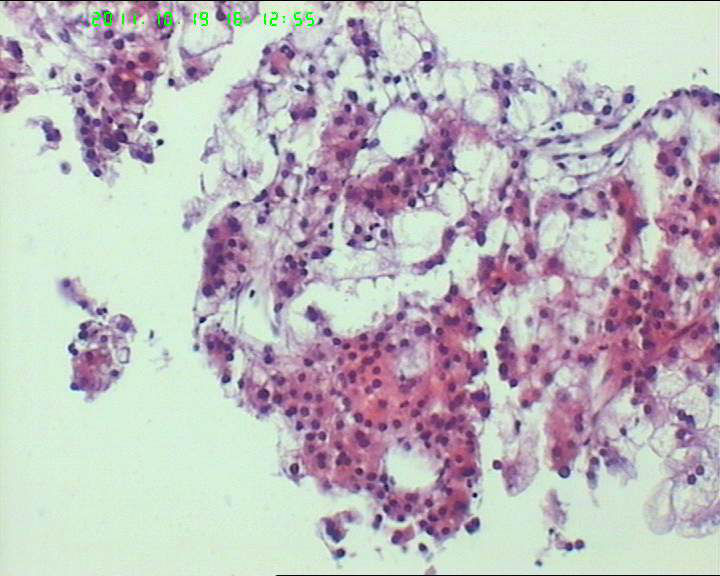

• 71岁男性肝脏占位,ct示低密灶,大三阳,afp高,转氨酶略高。该诊断什么呢?图2

图2